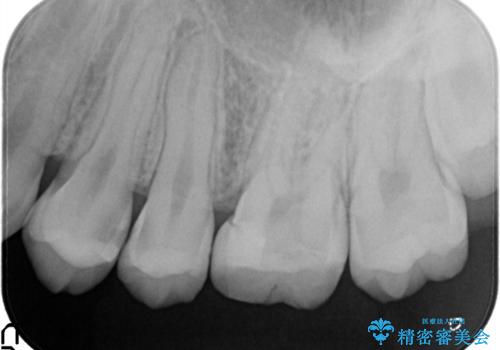

精密なむし歯の治療 セラミックインレー

- 定期健診にてむし歯を認めた患者さまです。

笑った時に見える部分だったためセラミックインレーにて修復しました。

保険治療で使える材料には制限があり、見た目だけでなく精度でも劣ります。当院でのセラミックインレーは歯とのつなぎ目を拡大鏡で確認して精度高く仕上げるため、むし歯のリスクを限りなく少なくできるよう治療します。